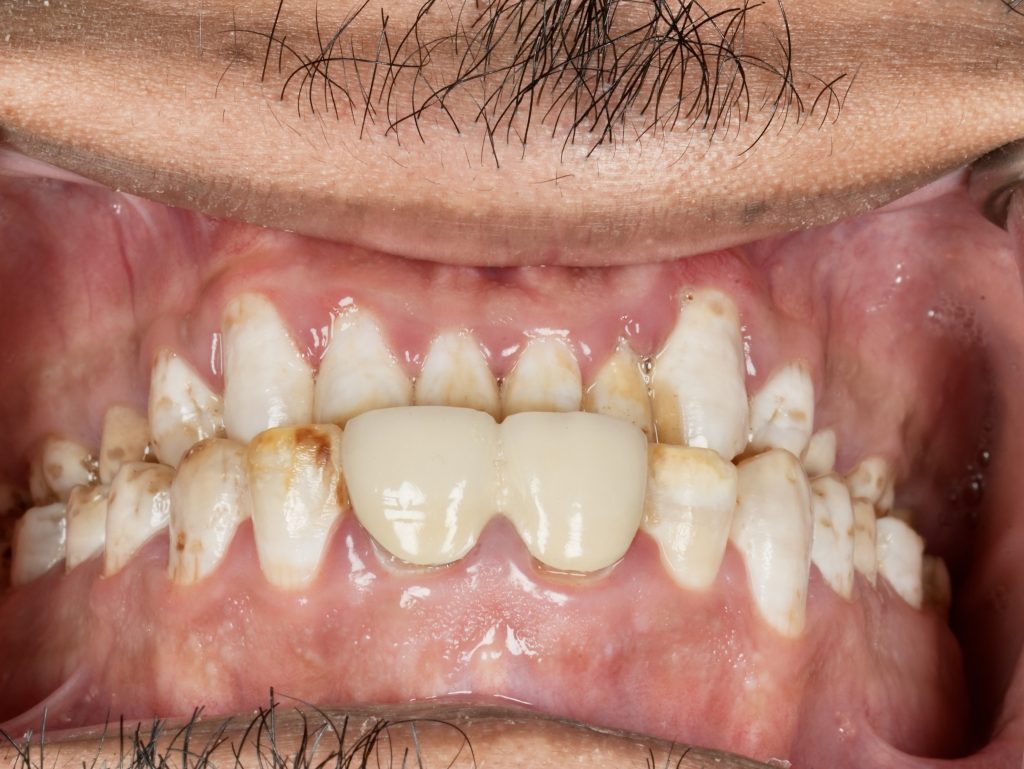

The patient sought esthetic improvement for uneven incisal edges, discolored anterior teeth, and disproportionate gingival display (Fig 1). A digital smile simulation and mock-up try-in were performed to assess tooth proportion, midline alignment, and incisal curvature. The plan prioritized enamel conservation and optical harmony.

Using silicone indexes derived from the mock-up, controlled minimal-thickness veneer preparations (0.3–0.5 mm) were carried out under microscope magnification to ensure uniform reduction and margin clarity (Fig 2). Finish lines were placed juxta-gingivally with soft-tissue protection using Teflon and double-cord isolation.